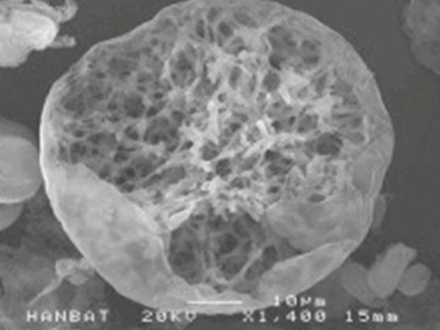

PLA성분이 분해되면서 콜라겐 등의

신생조직 생성을 촉진합니다.